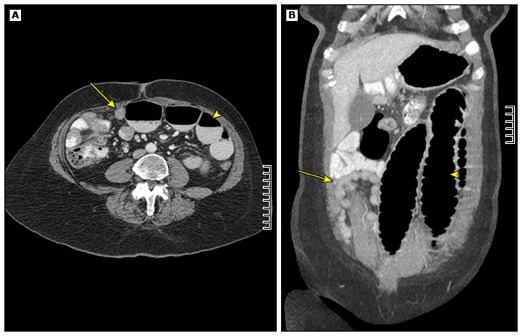

A 43 year old female with a history of type 2 diabetes, hyperlipidemia, and metastatic ovarian cancer presents to the emergency department with abdominal pain. She has had a week of constant nausea after her last chemotherapy infusion, and today began experiencing worsening nausea and new onset abdominal pain. Her vital signs show blood pressure 110/78 mm Hg, heart rate 104/min, respiratory rate 18/min, and oxygen saturation 97% on room air. Physical examination shows a distended abdomen that is diffusely tender to palpation. CT demonstrates the following findings.